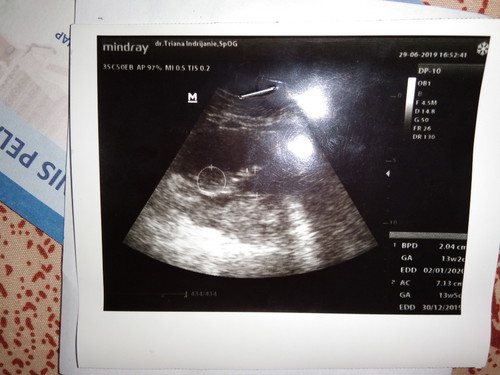

Itu UK janin 13week y bun.. kalo hitungan usg emng agk beda sama hitungan kita .. kita ngitung ny dr awal haid terakhir tp klo hitungan usg d hitung dr pas kelihatan kantong ny.. it normal kq bun.. slgi dktr bilang normal bunda sehat2 aj jg jd jgn d ambil pusing y.. mdh2n bunda dn debay sehat selalu

Di usg itu usia janin baru uk 13week bund, jadi belum bisa diukur BJ nya. Dan untuk janin ukuran 13week memang biasanya belum bisa terdeteksi JK nya.

BPD lingkar kepala AC lingkar perut GA UK janin EDD hpl Bun

Đọc thêmGA : usia janin kalo ga salah itu 13w5d bund ya blum 16 w

Itu 13w2d bun